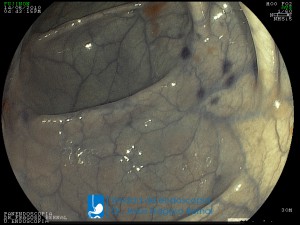

La Unidad de Endoscopía fue creada en 2002 por el Dr. Jesús Fragoso Bernal, es pionera en el estado por la utilización de la tecnología más avanzada, que nos permite ofrecer servicios integrales de diagnóstico y tratamiento para las enfermedades del aparato digestivo.